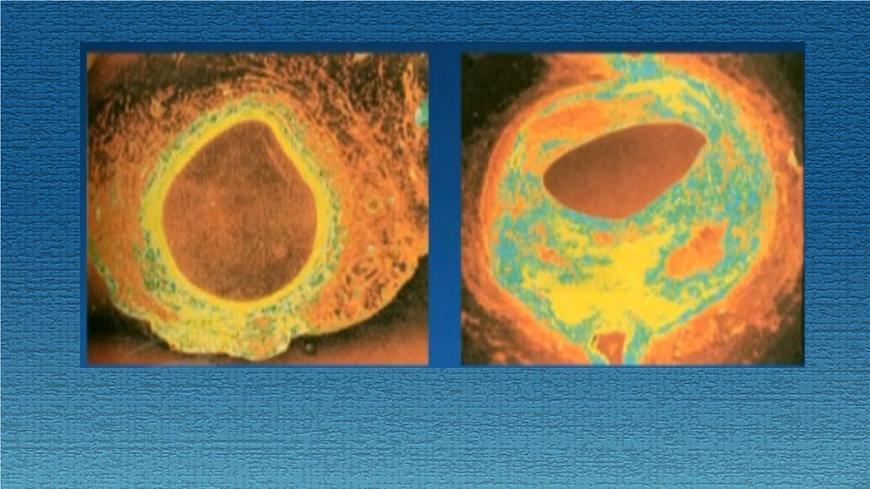

由于脂肪、胆固醇的堆积,管腔内壁出现黄色粥一样的斑块,这就是动脉硬化

动脉硬化会给血管带来什么影响?

如果冠状动脉硬化,会使心肌缺血,甚至堵塞。如果心肌暂时性缺血,出现胸闷、胸前区疼痛的症状,这就是心绞痛(冠心病);

如果冠状动脉被凝血堵塞,血液不能流通,心脏细胞会因得不到血液供应而死亡,严重时会危及生命,这就是心肌梗塞。

动脉硬化发生在脑部,会造成脑梗塞,即中风,中风时,患者会出现偏瘫、失语、意识障碍等,严重时会危及生命。

通常高血压和动脉硬化有密切联系。动脉硬化后,血管弹性变小,官腔变窄,血压就会增高,血压过高会增加心脏负担(收缩力度加大),严重时,使血管发生破裂,危害生命。